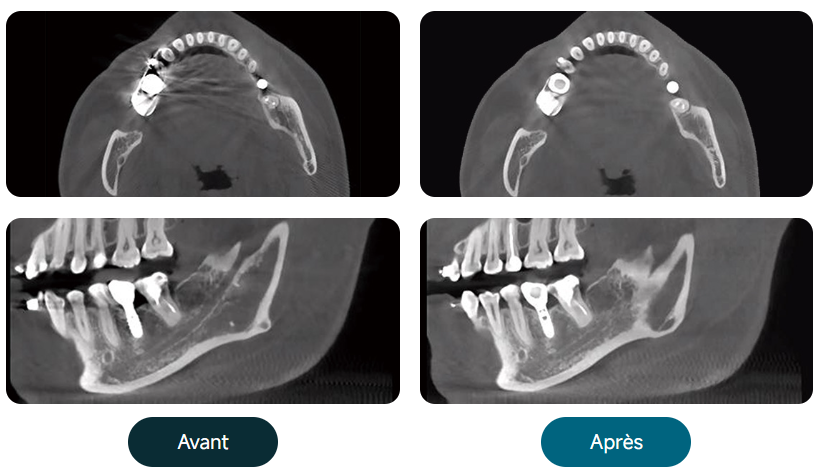

Algorithme de correction des mouvements du patient